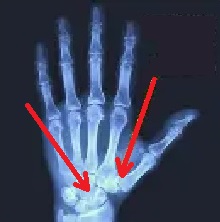

Bend your wrist like the picture below.

Now I challenge you to spread

your fingers apart!